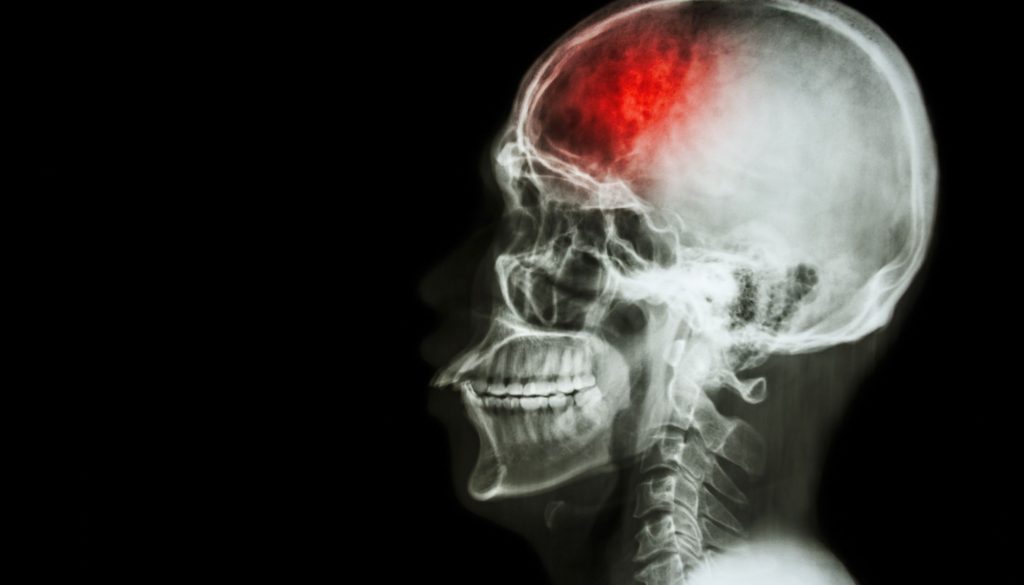

السكتة الدماغية تحدث عندما ينقطع تدفق الدم إلى جزء من الدماغ، ما يؤدي إلى تلف في الخلايا الدماغية. هناك نوعان رئيسيان من السكتات الدماغية:

2. **السكتة الدماغية النزفية**:

تحدث عندما تنفجر الأوعية الدموية في الدماغ، مما يتسبب في تسرب الدم إلى الأنسجة المحيطة.